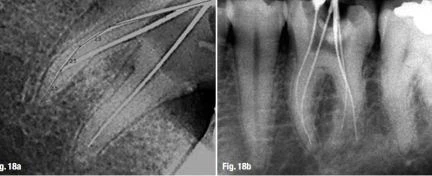

Mặc dù có rất nhiều ưu điểm và lợi ích khi sử dụng DR, nhưng nhiều báo cáo nhấn mạnh rằng chất lượng hình ảnh chung của X quang thông thường tốt hơn (Hình 18a & b). Khi dùng X quang thông thường và DR được để xác định WL, sau đó so sánh với dùng máy định vị điện tử, ta thấy rằng vị trí lỗ chóp khi xác định bằng máy định vị điện tử nằm cao hơn vì nhìn chung RM cho kết quả đo dài hơn thường có hiện tượng quá chóp.

Hình ảnh RVG của răng cối lớn hàm dưới

Hình 18a & b: Hình ảnh RVG của răng cối lớn hàm dưới (a) và X-quang thông thường (b).